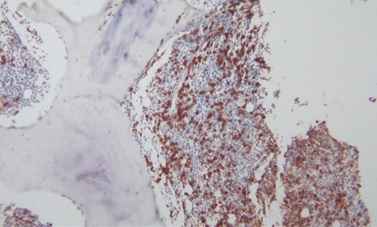

Bone marrow aspiration and biopsy from the posterior iliac crest demonstrated erythroid hyperplasia, normal maturation of granulocytic series with morphologically abnormal lymphocytes demonstrating cytoplasmic villous projection (Figure 2), erythroid hyperplasia with left shifted maturation, with reduced myelopoiesis and megakaryopoiesis. Bone marrow aspiration biopsy stained with CD20 demonstrated an infiltrate of small lymphoid cells positive for CD20, CD79a, kappa light chain and negative for CD3, CD5, CD10, Tdt, CD23 and CD34. Microscopically there were lymphoid cells showing interstitial and paratrabecular nodules (Figure 3).

Figure 2.  Lymphocytes with villous projections in bone marrow aspiration.

Figure 3. Bone marrow trephine biopsy with CD 20 stain.